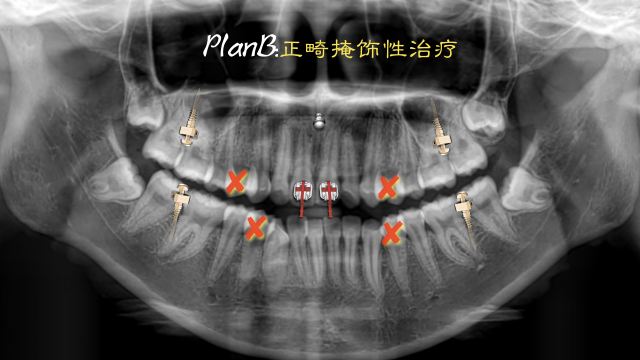

术后总结